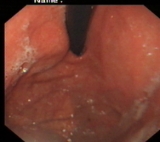

萎缩胃表现

内镜下表现:黏膜红白相间,以白色为主,黏膜皱襞变平或消失,部分黏膜血管显露,可伴有黏膜颗粒或结节状等表现。如伴有肠化生于电子染色窄带成像放大内镜(NBI ME)下发现胃粘膜上皮细胞表面的脑回样结构嵴部的纤细浅蓝色线样结构。病理活检可进一步确诊。